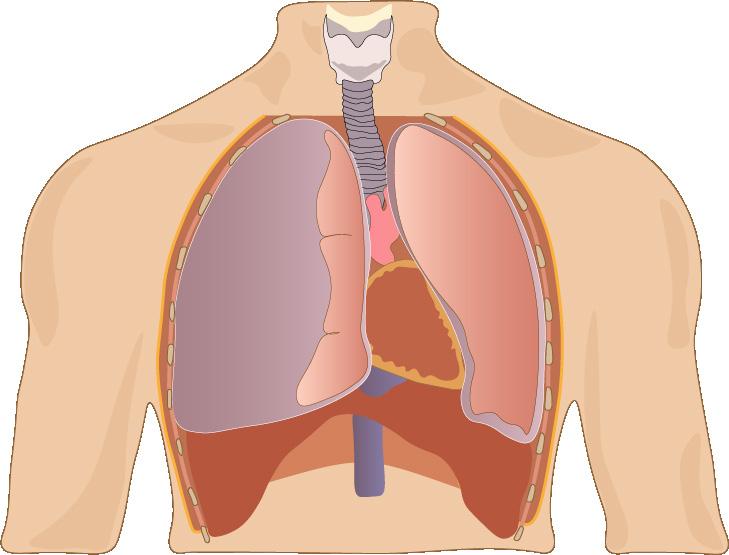

Acumulación de sangre en el espacio pericárdico → ↓diástole (llenado ventricular) → compromiso hemodinámico (shock obstructivo).

Diagnóstico

Dolor torácico, disnea y / o taquipnea (ENAM 2014, ENAM 2012, ENAM 2011, ENAM 2017, ENAM 2020, ENAM EXTRA 2021)

Tríada de Beck

♦ Hipotensión arterial (↓PA)

♦ Ingurgitación yugular (↑PVC)

♦ Ruidos cardíacos apagados